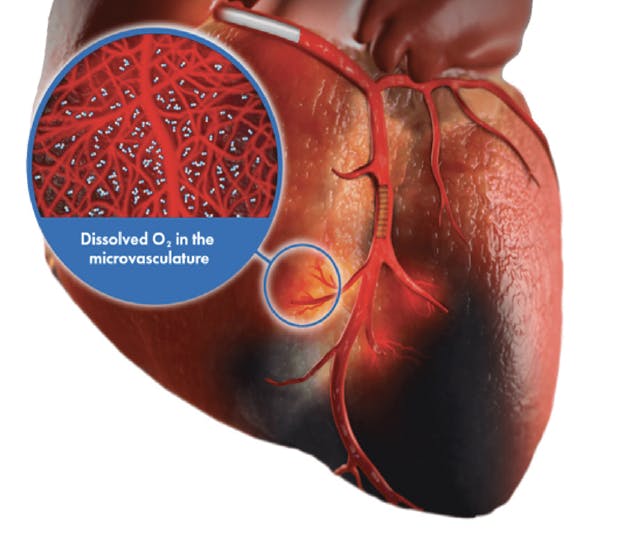

SSO2 Therapy (Figure 1) is a one-time, 60-minute therapy delivering high levels of dissolved oxygen directly to the left anterior descending (LAD) artery immediately after percutaneous coronary intervention (PCI) for anterior ST-segment elevation myocardial infarction (STEMI) and has been shown to reduce infarct size by 26% in clinical studies.1 Infarct size is directly correlated with all-cause mortality and heart failure hospitalization within 1 year.2

Figure 1. SSO2 therapy delivered via catheter into the LAD post-PCI.